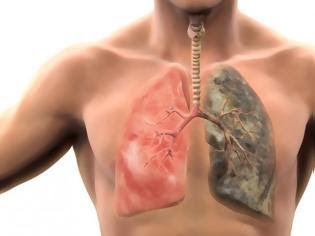

Ο καθένας ξέρει ότι το κάπνισμα είναι η κύρια αιτία του καρκίνου των πνευμόνων, των καρδιαγγειακών παθήσεων και άλλων απειλητικών για τη ζωή χρόνιων παθήσεων. Συχνά οι καπνιστές θεωρούν πως, αν κόψουν το κάπνισμα θα μπορέσουν να ανακτήσουν πλήρως την υγεία των πνευμόνων τους. Σύμφωνα με τους ειδικούς, αυτό είναι μόνο εν μέρει αλήθεια.

Ενώ ορισμένα τμήματα των πνευμόνων μπορεί να θεραπευτούν από την βλάβη που προκαλείται από το κάπνισμα, δυστυχώς όμως το μεγαλύτερο μέρος της καταστροφής είναι μόνιμο.

Το κάπνισμα καταστρέφει τις μικροσκοπικές “τρίχες” στους πνεύμονές σας στους ανώτερους αεραγωγούς. Η κύρια λειτουργία τους είναι να προστατεύσουν τους πνεύμονες από τις λοιμώξεις, είτε ιογενείς είτε βακτηριακές. Αυτό το σύστημα εν γένει, καταστρέφεται από τον καπνό των τσιγάρων και έτσι μειώνεται η αποτελεσματικότητά του. Εντούτοις, οι στατιστικές δείχνουν, ότι για τους ανθρώπους που έχουν κόψει το κάπνισμα μειώνεται ο κίνδυνος εμφάνισης καρκίνου του πνεύμονα.